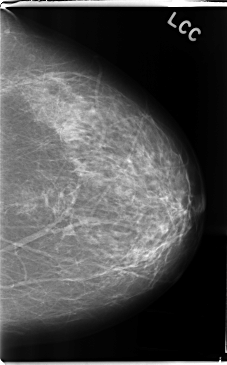

C_0242_1.LEFT_CC

LEFT_CC LINES 4736 PIXELS_PER_LINE 2944 BITS_PER_PIXEL 12 RESOLUTION 50 NON_OVERLAY